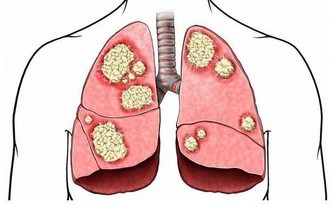

3、經常咳嗽,或者出現痰中帶血:肺癌是我國發病率和死亡率最高的癌症。肺癌患者中通常為長期抽煙的人,肺部腫瘤初期一般都是表現為各種慢性肺炎,其表現就是咳嗽(大家一定要和哮喘、支氣管炎區分開來)。